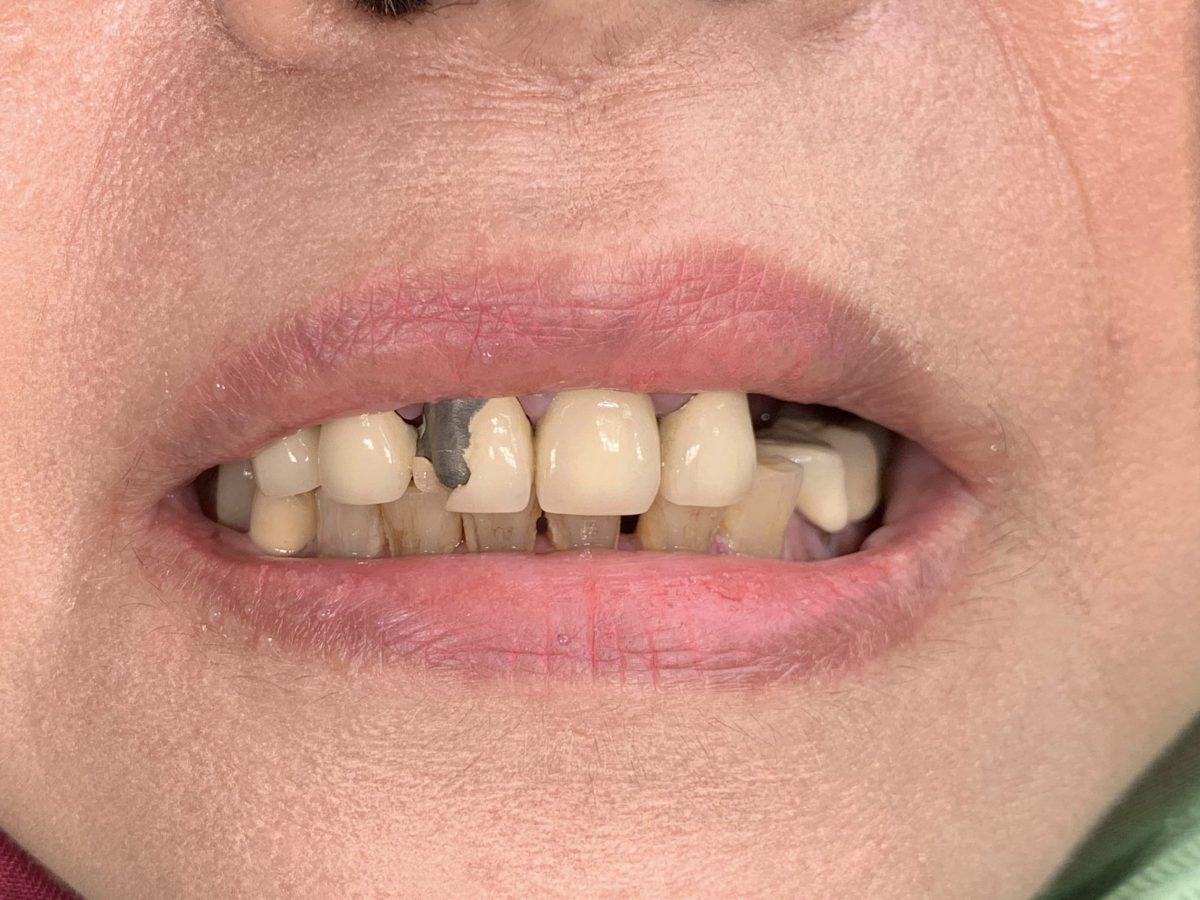

Full mouth rehabilitation is a comprehensive dental treatment designed to restore both function and aesthetics for patients with severely worn, damaged, missing, or failing teeth.

Treatment may include a combination of:

* crowns

* veneers

* dental implants

* bridges

* gum treatment

* bite rehabilitation

Each treatment plan is customized based on the patient’s oral condition and long-term goals.